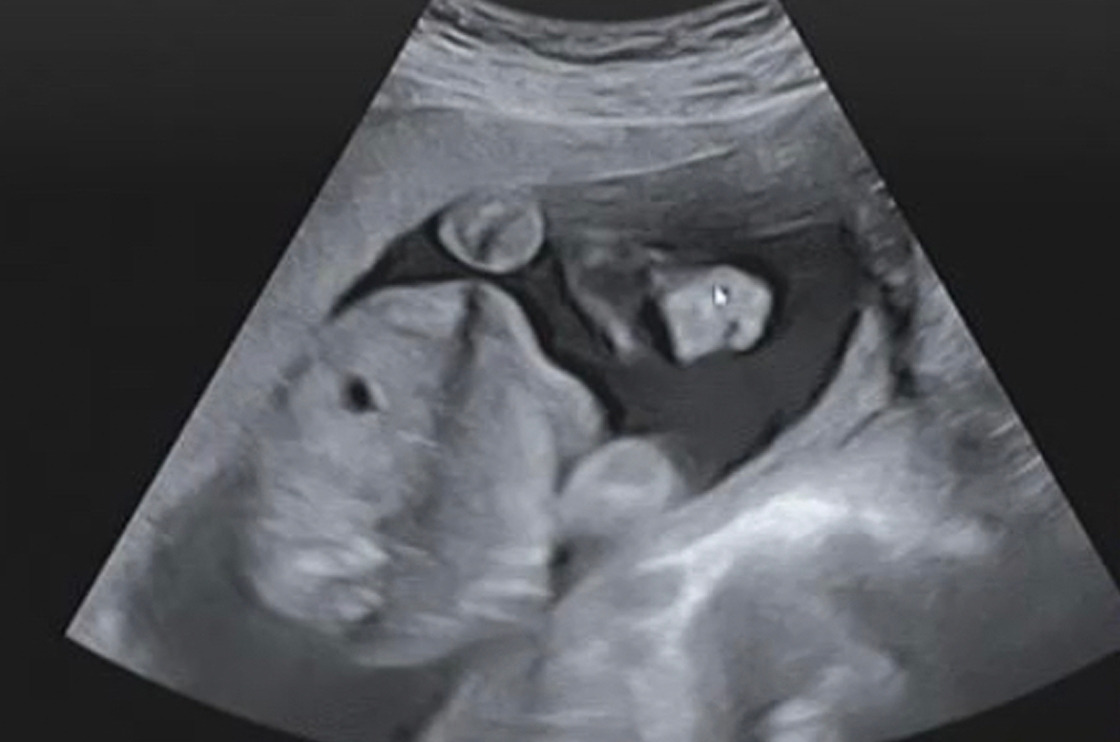

정밀검사를 했다. 꽤 오랜 시간 초음파로 이것저것을 확인하는 검사였다. 심장이 뛰는 모습을 오랫동안 볼 수 있었는데, 그 순간이 제일 찡했다. 매일 ‘너는 뭐하니?’, ‘뭘 하긴 하는 거니?’라고 물었는데, 정말 열심히 살아가고 있구나. 280days라는 어플에 익숙해져서, 뱃속의 꾸꾸가 그렇게 생겼다고 믿고 있었는데, 오늘 꾸꾸의 실체를 보고는 조금 깜짝 놀랐다. 물론 턱과 콧구멍이 얼굴이 전부이긴 했지만. 그런데 아내는 ‘귀엽다’라고 말했다. 역시 이길 수 없는 모성애인가. 정밀 검사의 결과 꾸꾸의 머리는 주수보다 조금 크고, 배는 조금 더 크고, 허벅지 길은 조금 짧다고 한다.ㅋㅋㅋㅋ 짜식.

_ 그녀의 콧구멍, 내 콧구멍 같아....